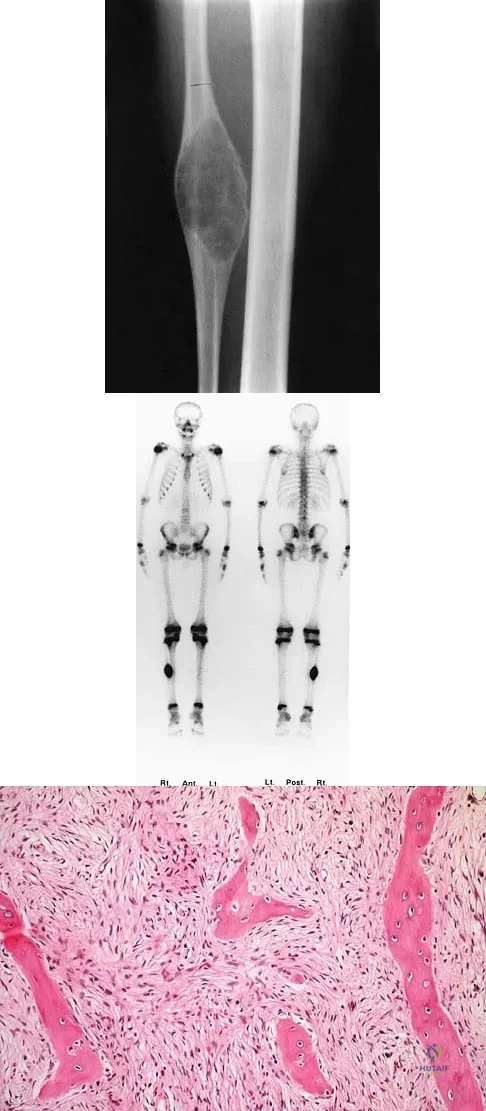

A 10-year-old child has leg discomfort with activity. A radiograph, bone scan, and biopsy specimen are shown in Figures 1a through 1c. What is the most likely diagnosis?